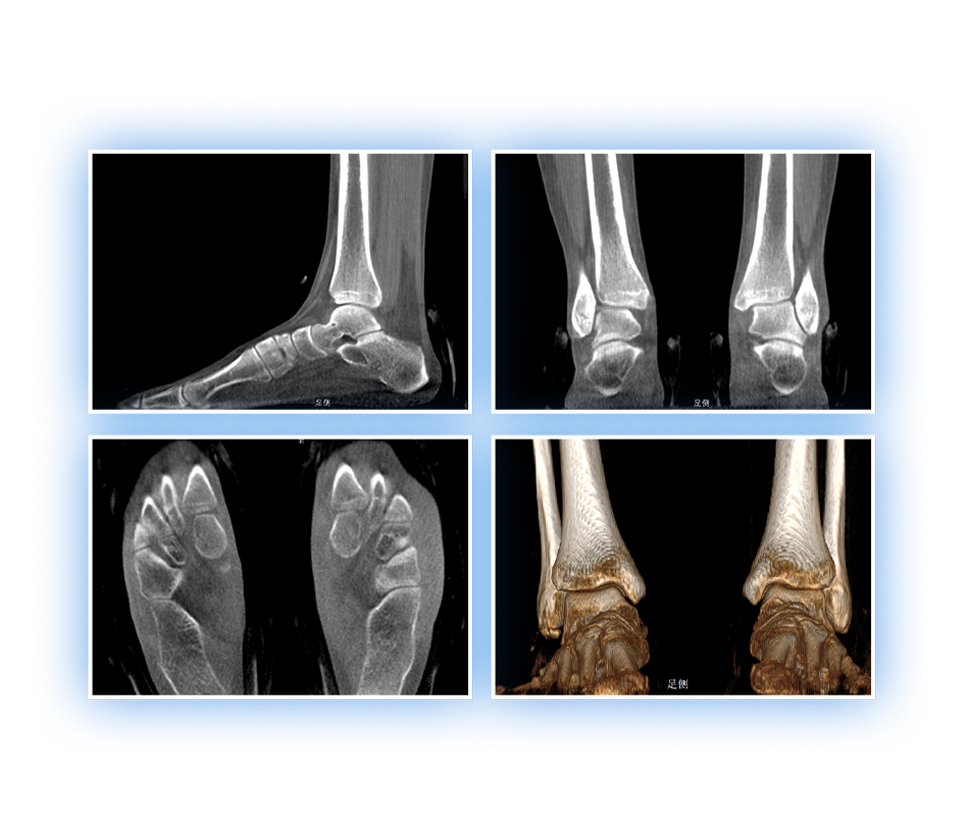

獨特的負重位三維影像

填補常規(guī)CT/MR空白

助力術(shù)前規(guī)劃和術(shù)后評估

獨特的負重位三維影像

足踝

2D+3D一站式快速檢查

支持雙腿或雙側(cè)髖關(guān)節(jié)掃描 | 方便對比,降低漏診誤診